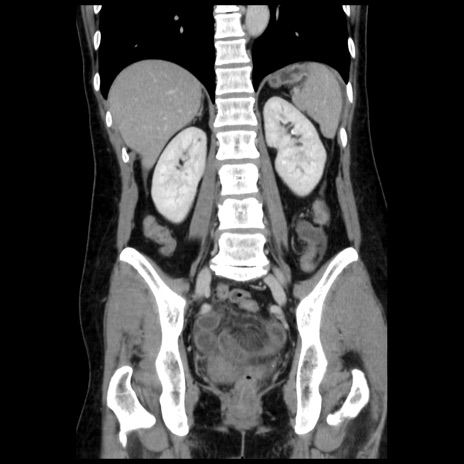

症例10(冠状断像)

【症例】 50歳代女性

【主訴】 腹痛

【現病歴】前日生レバーを食べた。今朝に排便あり。 昼前に突然発症の腹痛を生じ、当院救急外来を受診した。

【既往歴】 子宮筋腫にてで子宮全摘後

【身体所見】 意識清明、腹部:平坦、軟、下腹部やや左を中心に圧痛・反跳痛あり、筋性防御あり

【データ】WBC 7800、CRP 0.07